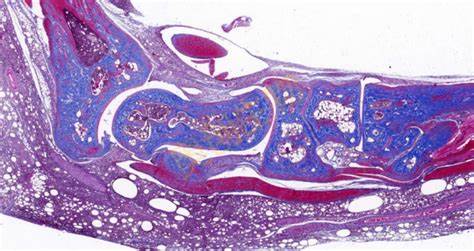

HE染色(苏木精 - 伊红染色)是组织学和病理学中最常用的染色方法,用于观察细胞和组织的形态结构。以下是关于HE染色的详细介绍:**一、染色原理**1. 苏木精染色原理 - 苏木精是一种碱性染料,它可以与细胞核中的酸性物质(如DNA和RNA)结合。苏木精本身没有颜色,在经过氧化后变成苏木精氧化产物,带有正

19055147252 立即咨询HE染色(苏木精 - 伊红染色)是组织学和病理学中最常用的染色方法,用于观察细胞和组织的形态结构。以下是关于HE染色的详细介绍:

**四、结果观察与分析**

1. 细胞核

- 正常情况下,细胞核被染成蓝紫色,颜色深浅均匀。可以观察细胞核的大小、形状、位置以及核内结构(如核仁)。例如,在肿瘤细胞中,细胞核通常比正常细胞的细胞核大,形状不规则,核仁明显增大。

2. 细胞质

- 细胞质呈粉红色。通过观察细胞质的染色情况,可以了解细胞的功能状态和分化程度。例如,在分泌细胞中,细胞质可能含有较多的分泌颗粒,染色后可以看到细胞质中有一些深色的小点。

3. 组织和细胞形态

- 可以观察组织的整体结构,如上皮组织的层次、结缔组织的纤维排列、肌肉组织的肌纤维走向等。同时,也可以观察细胞之间的连接方式(如紧密连接、桥粒等)和细胞在组织中的分布情况。例如,在正常的皮肤组织中,表皮的角质形成细胞从基底层到角质层呈现出有规律的分层排列。